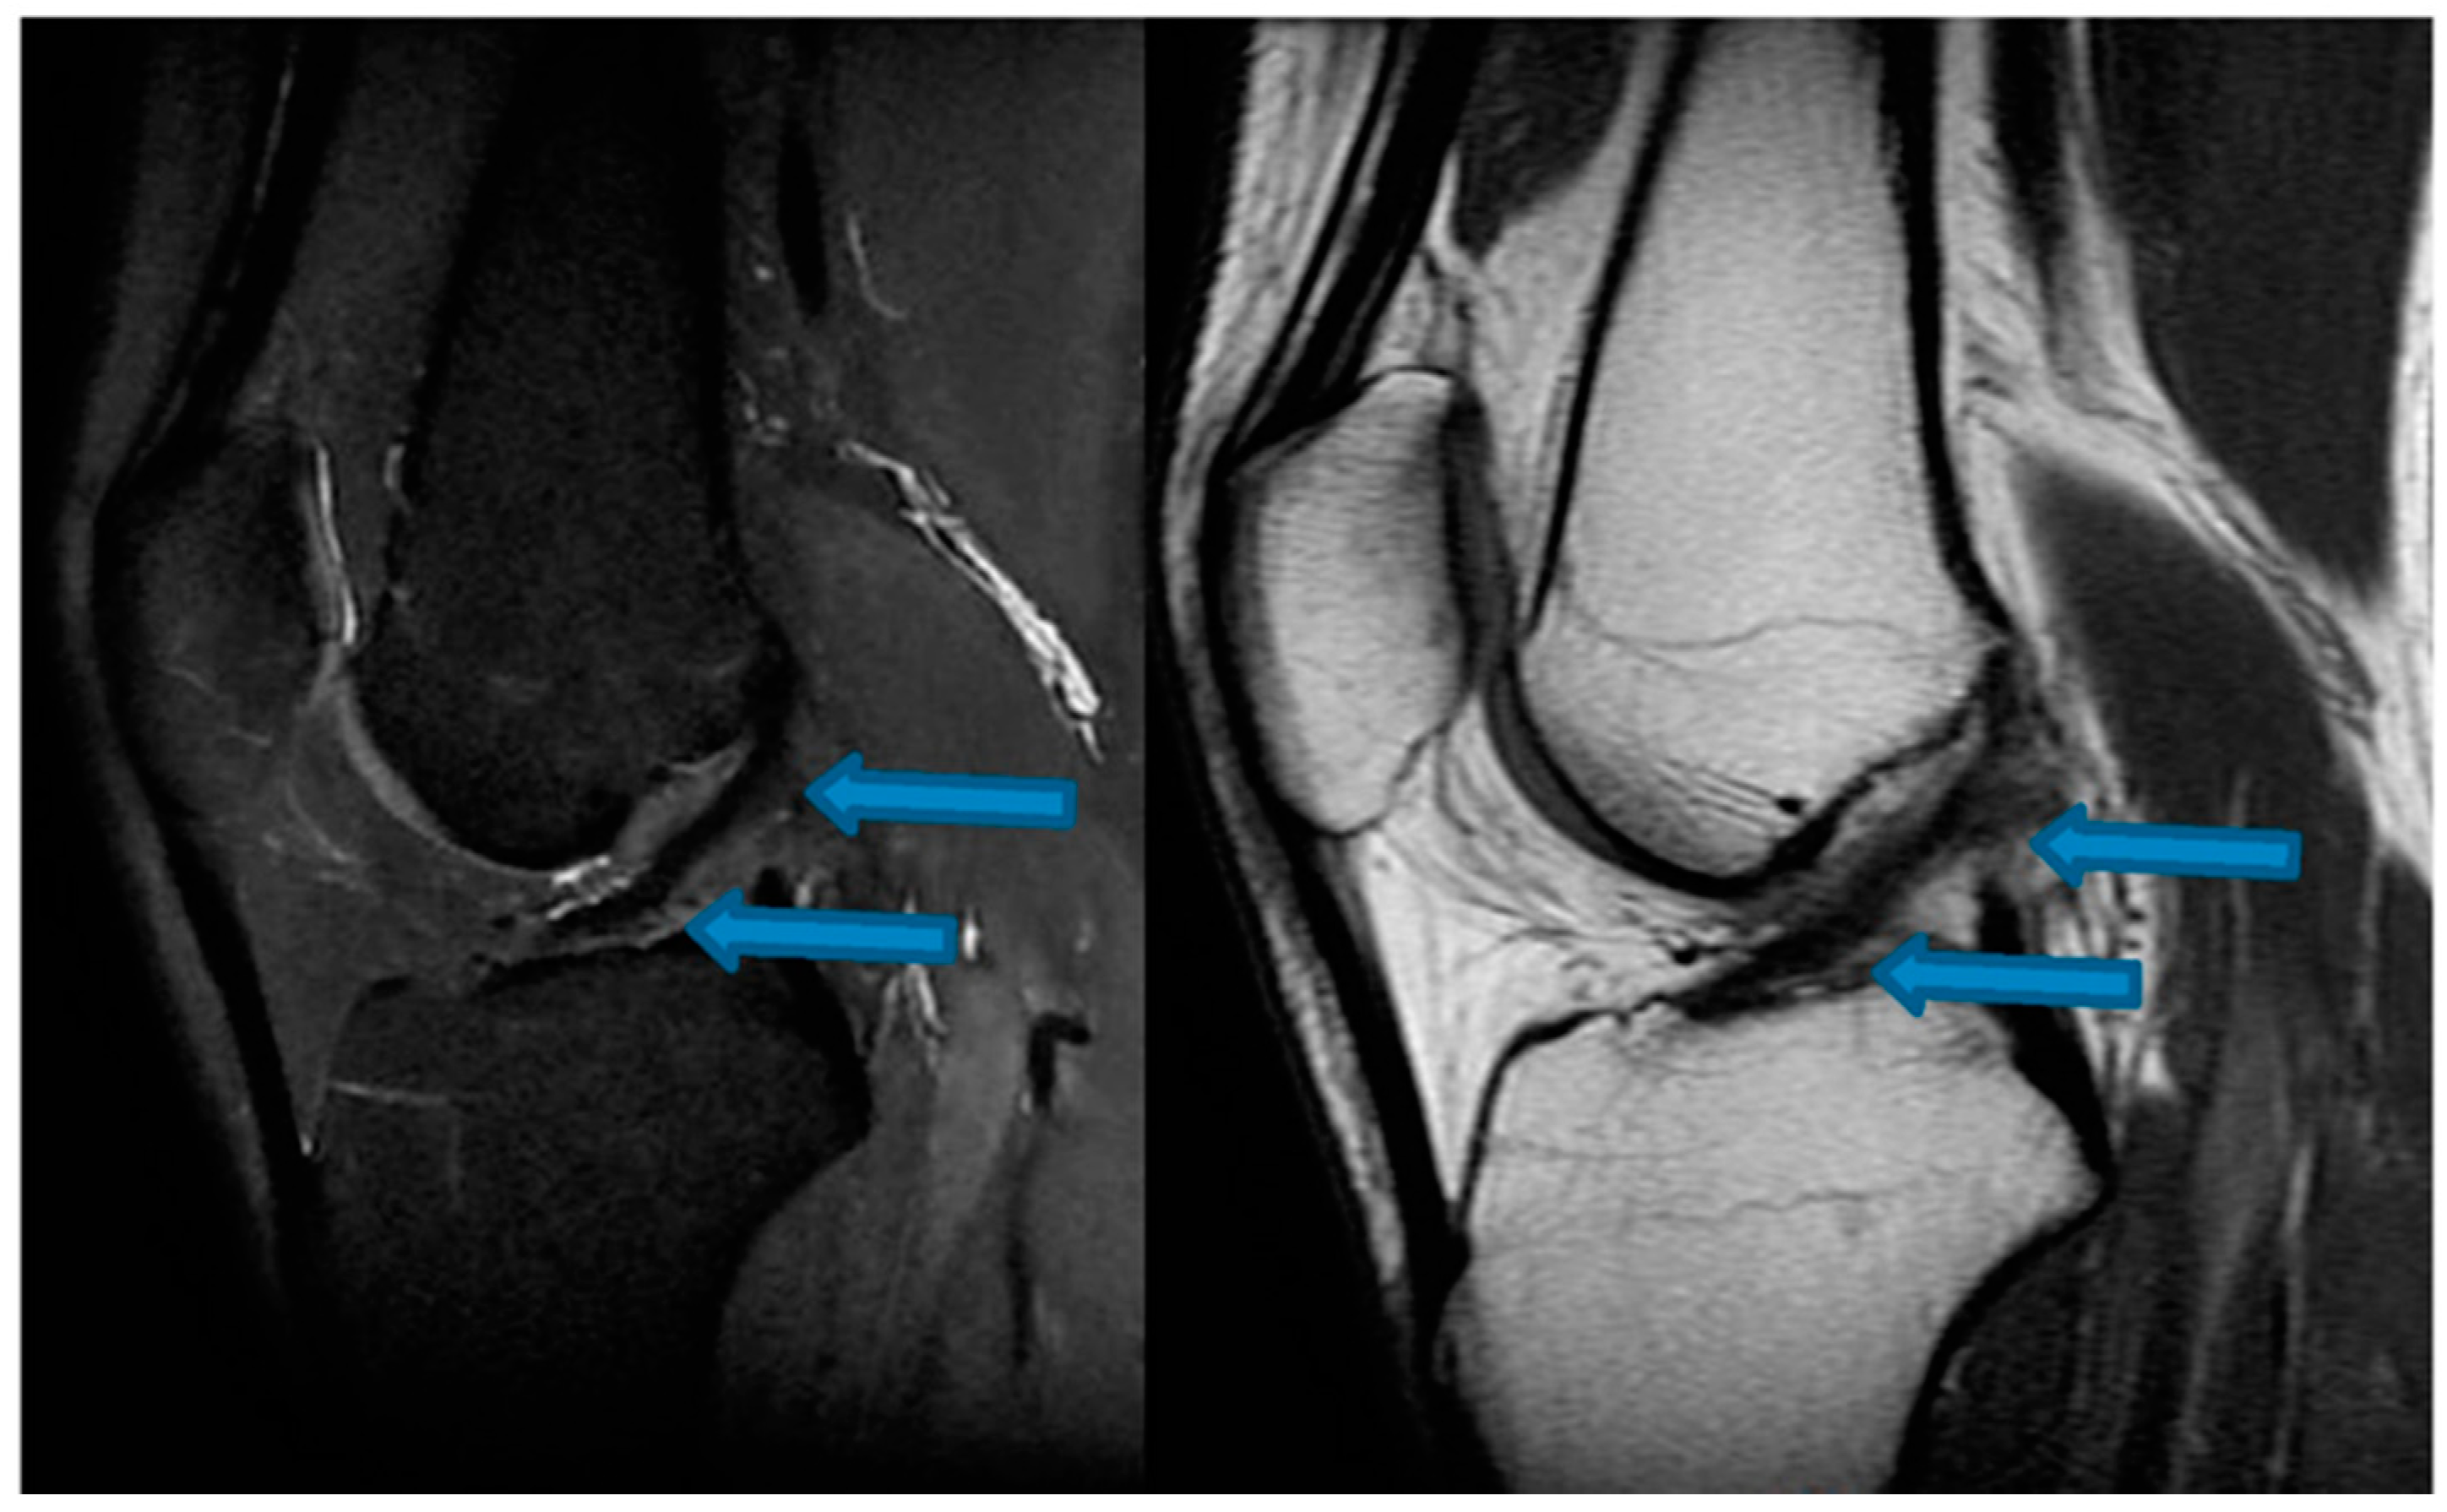

| 24 December 2021 | MRI scans confirming signs of complete ACL, MCL and medial meniscus healing |